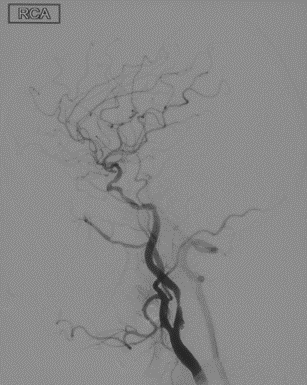

辅助检查(DSA)

R-CA

波科支架怎么样径技-弓上病例大赏|第210期·右侧颈内动脉球囊扩张术+支架植入术_https://www.jmylbn.com_新闻资讯_第12张

• 病例特点:右侧颈内动脉C1段重度狭窄,致远端供血区域脑梗死,手术指征明确;